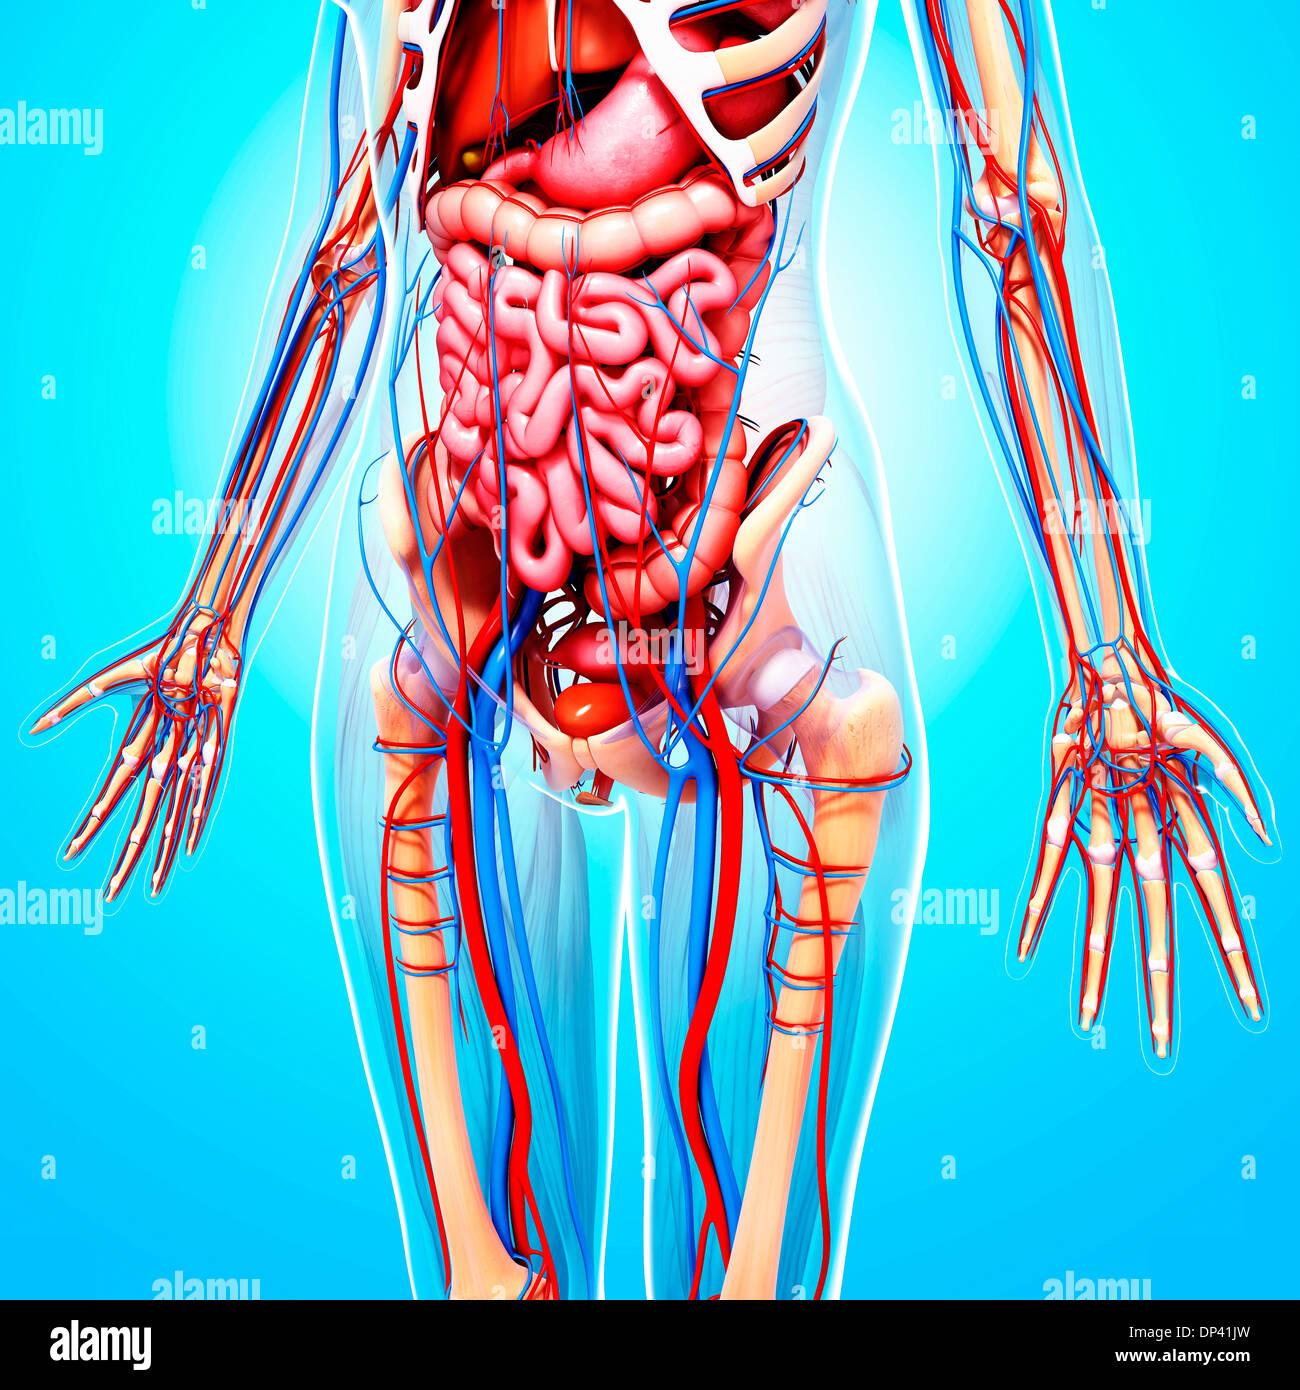

www.alamy.com3d Rendered Illustration Of The Female Anatomy Stock Photo - Alamy

www.alamy.com3d Rendered Illustration Of The Female Anatomy Stock Photo - Alamy

fineartamerica.com3d Rendered Illustration Of The Female Anatomy Stock Photo - Alamy

fineartamerica.com3d Rendered Illustration Of The Female Anatomy Stock Photo - Alamy